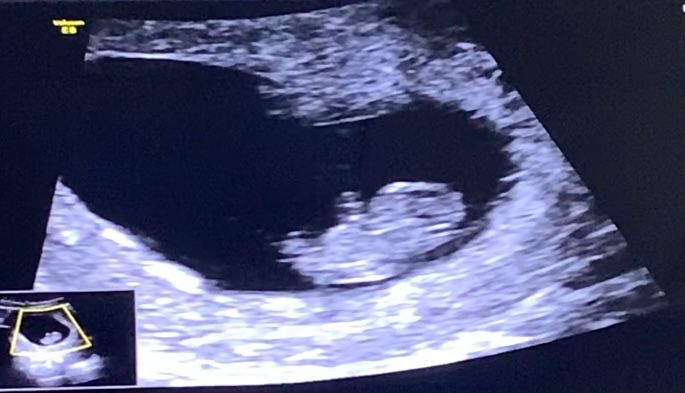

Изображение

Врываемся в 37ю неделю🥳

Пройдено много переживаний по поводу коричневых выделений, и наконец-то мы нашли этому объяснение на последнем УЗИ🙏🏼